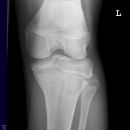

Kniegelenk